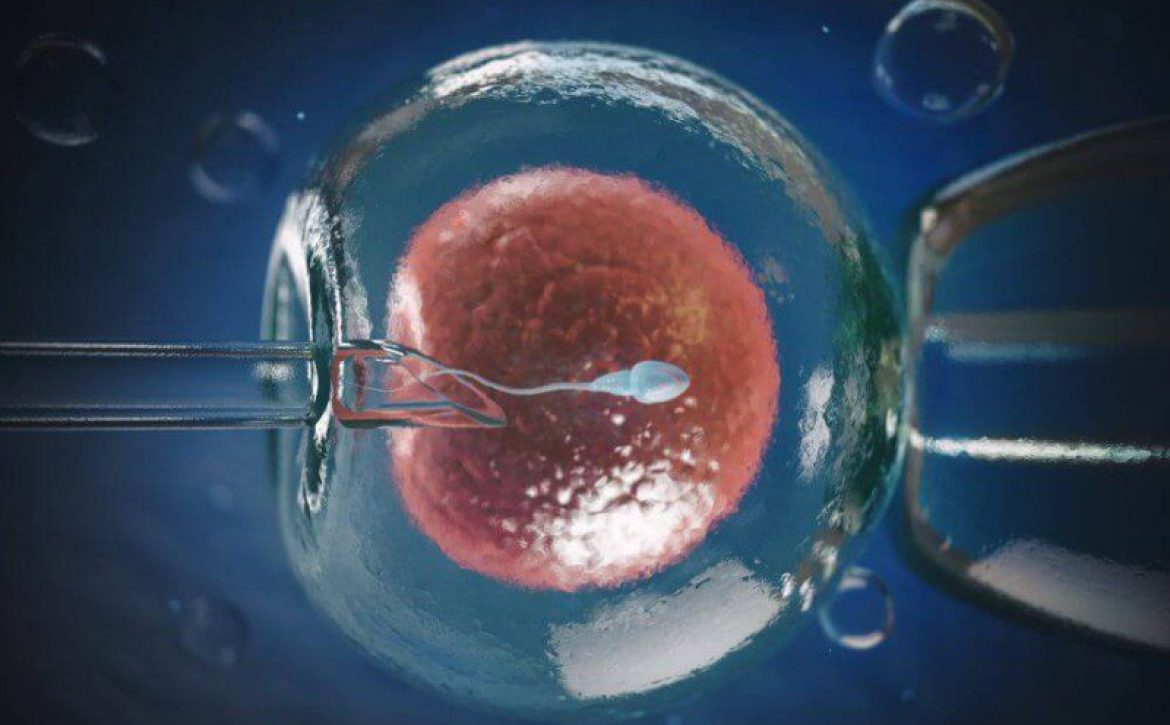

عملية الحقن المجهري

: الحقن المجهري هي حقن حيوان منوي سليم مباشرة في البويضة لتسهيل عملية الإخصاب.

وهذا مفيد بشكل خاص إذا كان لدى الشريك الذكر عدد منخفض من الحيوانات المنوية أو ضعف حركة الحيوانات المنوية بسبب عامل وراثي.